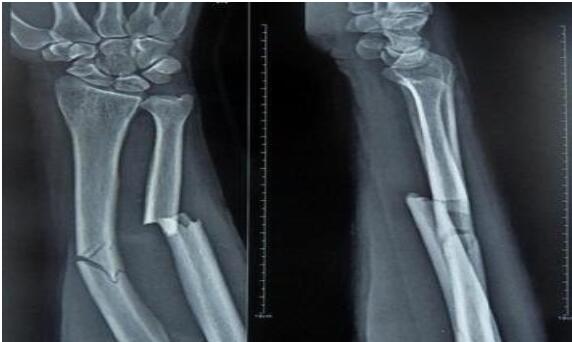

山丹接骨法是一種民間治療手段。山丹縣東樂鄉村民姜多明師從其父,掌握了接骨這門民間絕技。姜多明家族接骨已有上百年歷史,其父親是東樂一帶有名的中醫。改革開放前,由于農村醫療條件有限,這一技術在農村發揮了很大作用,給人民群眾減輕了不少身體上的痛苦。這項接骨技術同時也適用于給牲畜接骨。骨折愈合過程是一個高度復雜和有序的精細過程,姜多明所用的中醫傳統接骨法對骨折愈合起到了其他藥品不可替代的作用,效果很好。這種傳統的接骨方法極為簡潔,不用石膏,只用中草藥加雞蛋清,中藥主要起治療作用,蛋清起固定作用。治療周期較短,小孩子7—8天,傷勢較重的最多1月;成人根據傷勢而定,最多40—50天;牲畜所用天數根據情況而定。 2010年7月6日,山丹接骨法(民間傳統接骨法)被張掖市人民政府列入第二批張掖市非物質文化遺產代表性項目名錄。保護單位:張掖市山丹縣文化館。